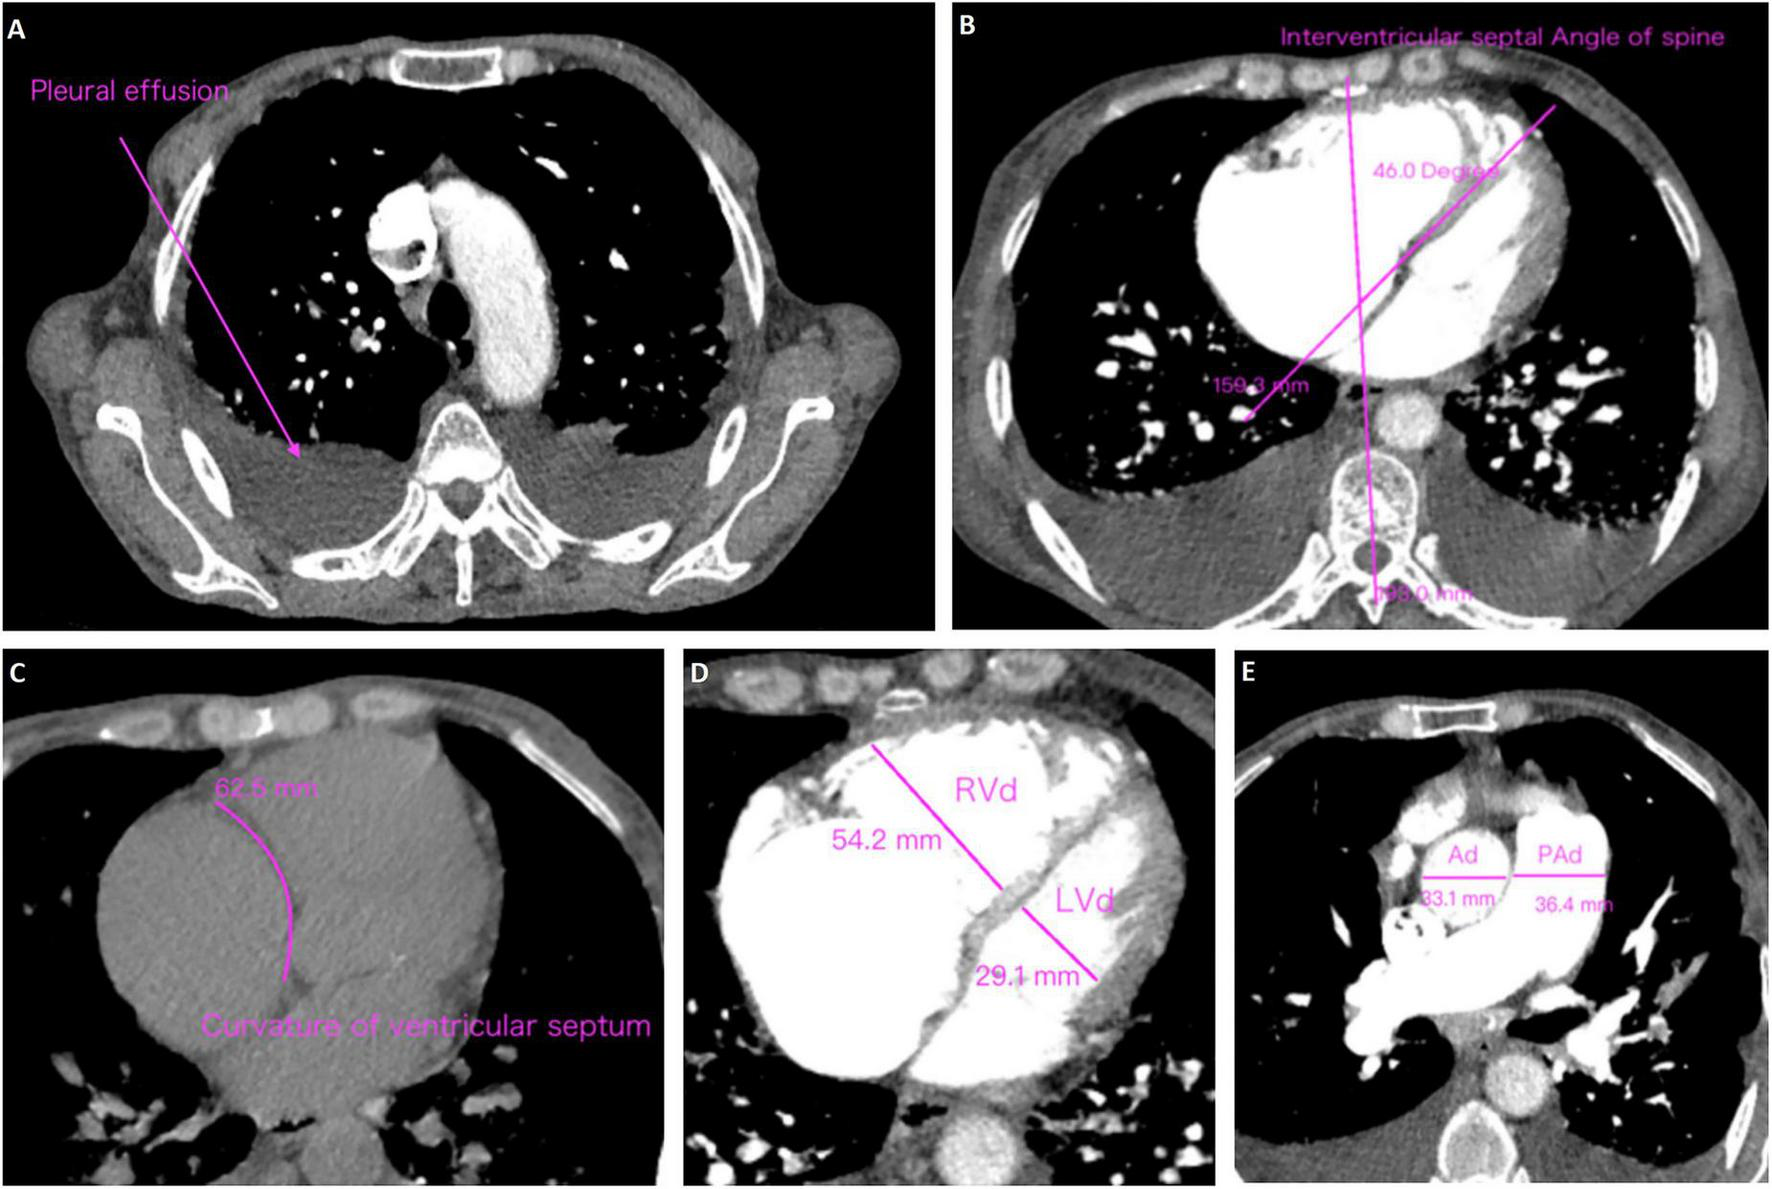

3.3 CTA characteristics

CT angiography is increasingly recognized as a valuable diagnostic tool for CTEPH due to its ability to provide rapid, non-invasive visualization of the pulmonary vasculature and facilitate the evaluation of right heart load. Unlike echocardiography which primarily evaluates cardiac functional consequences, CTA directly delineates pulmonary arterial obstructions, thrombus morphology, and small-vessel pathology, thereby enhancing diagnostic accuracy. Accordingly, pulmonary CTA data were collected for all subjects to comprehensively assess the radiologic characteristics of CTEPH in high-altitude populations (Table 2 and Supplementary Table 2). The results showed that patients in CTEPH group were more likely to have enlarged left upper pulmonary bronchus diameter (P = 0.002), a reduced cardiothoracic ratio (P = 0.010), and a thinner interventricular septum (IVS) (P = 0.038). Additionally, we analyzed pleural effusion, ventricular septum curvature, and spinal cord interventricular septum angle in both the PE and CTEPH groups (Figure 1) (29). The results indicated no statistically significant differences in these parameters between the two groups. Importantly, pulmonary embolism in CTEPH patients were more likely to occur in tertiary pulmonary arteries (P = 0.008). This may be due to the smaller diameter of subsegmental arteries (diameter < 2 mm), making them more prone to complete thrombotic occlusion (30), or due to impaired right heart venous return propelling thrombi toward distal vessels (31).

FIGURE 1

Methods of measurement and judgment of CTA signs. (A) Pleural effusion; (B) curvature of ventricular septum; (C) interventricular septal angle of spine; (D) right ventricular diameter (RVd)/left ventricular diameter (LVd); (E) pulmonary artery diameter (PAd)/aorta diameter (Ad).